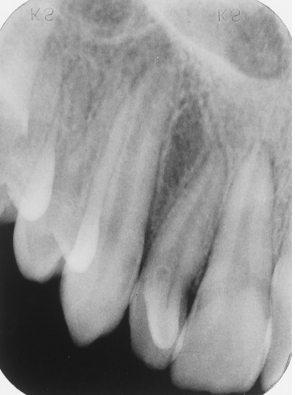

Study the lateral incisor. What feature(s) can you not regarding this tooth?

accessory lingual cusp

dens in dente

dilacerated crown

peg lateral

all of the above